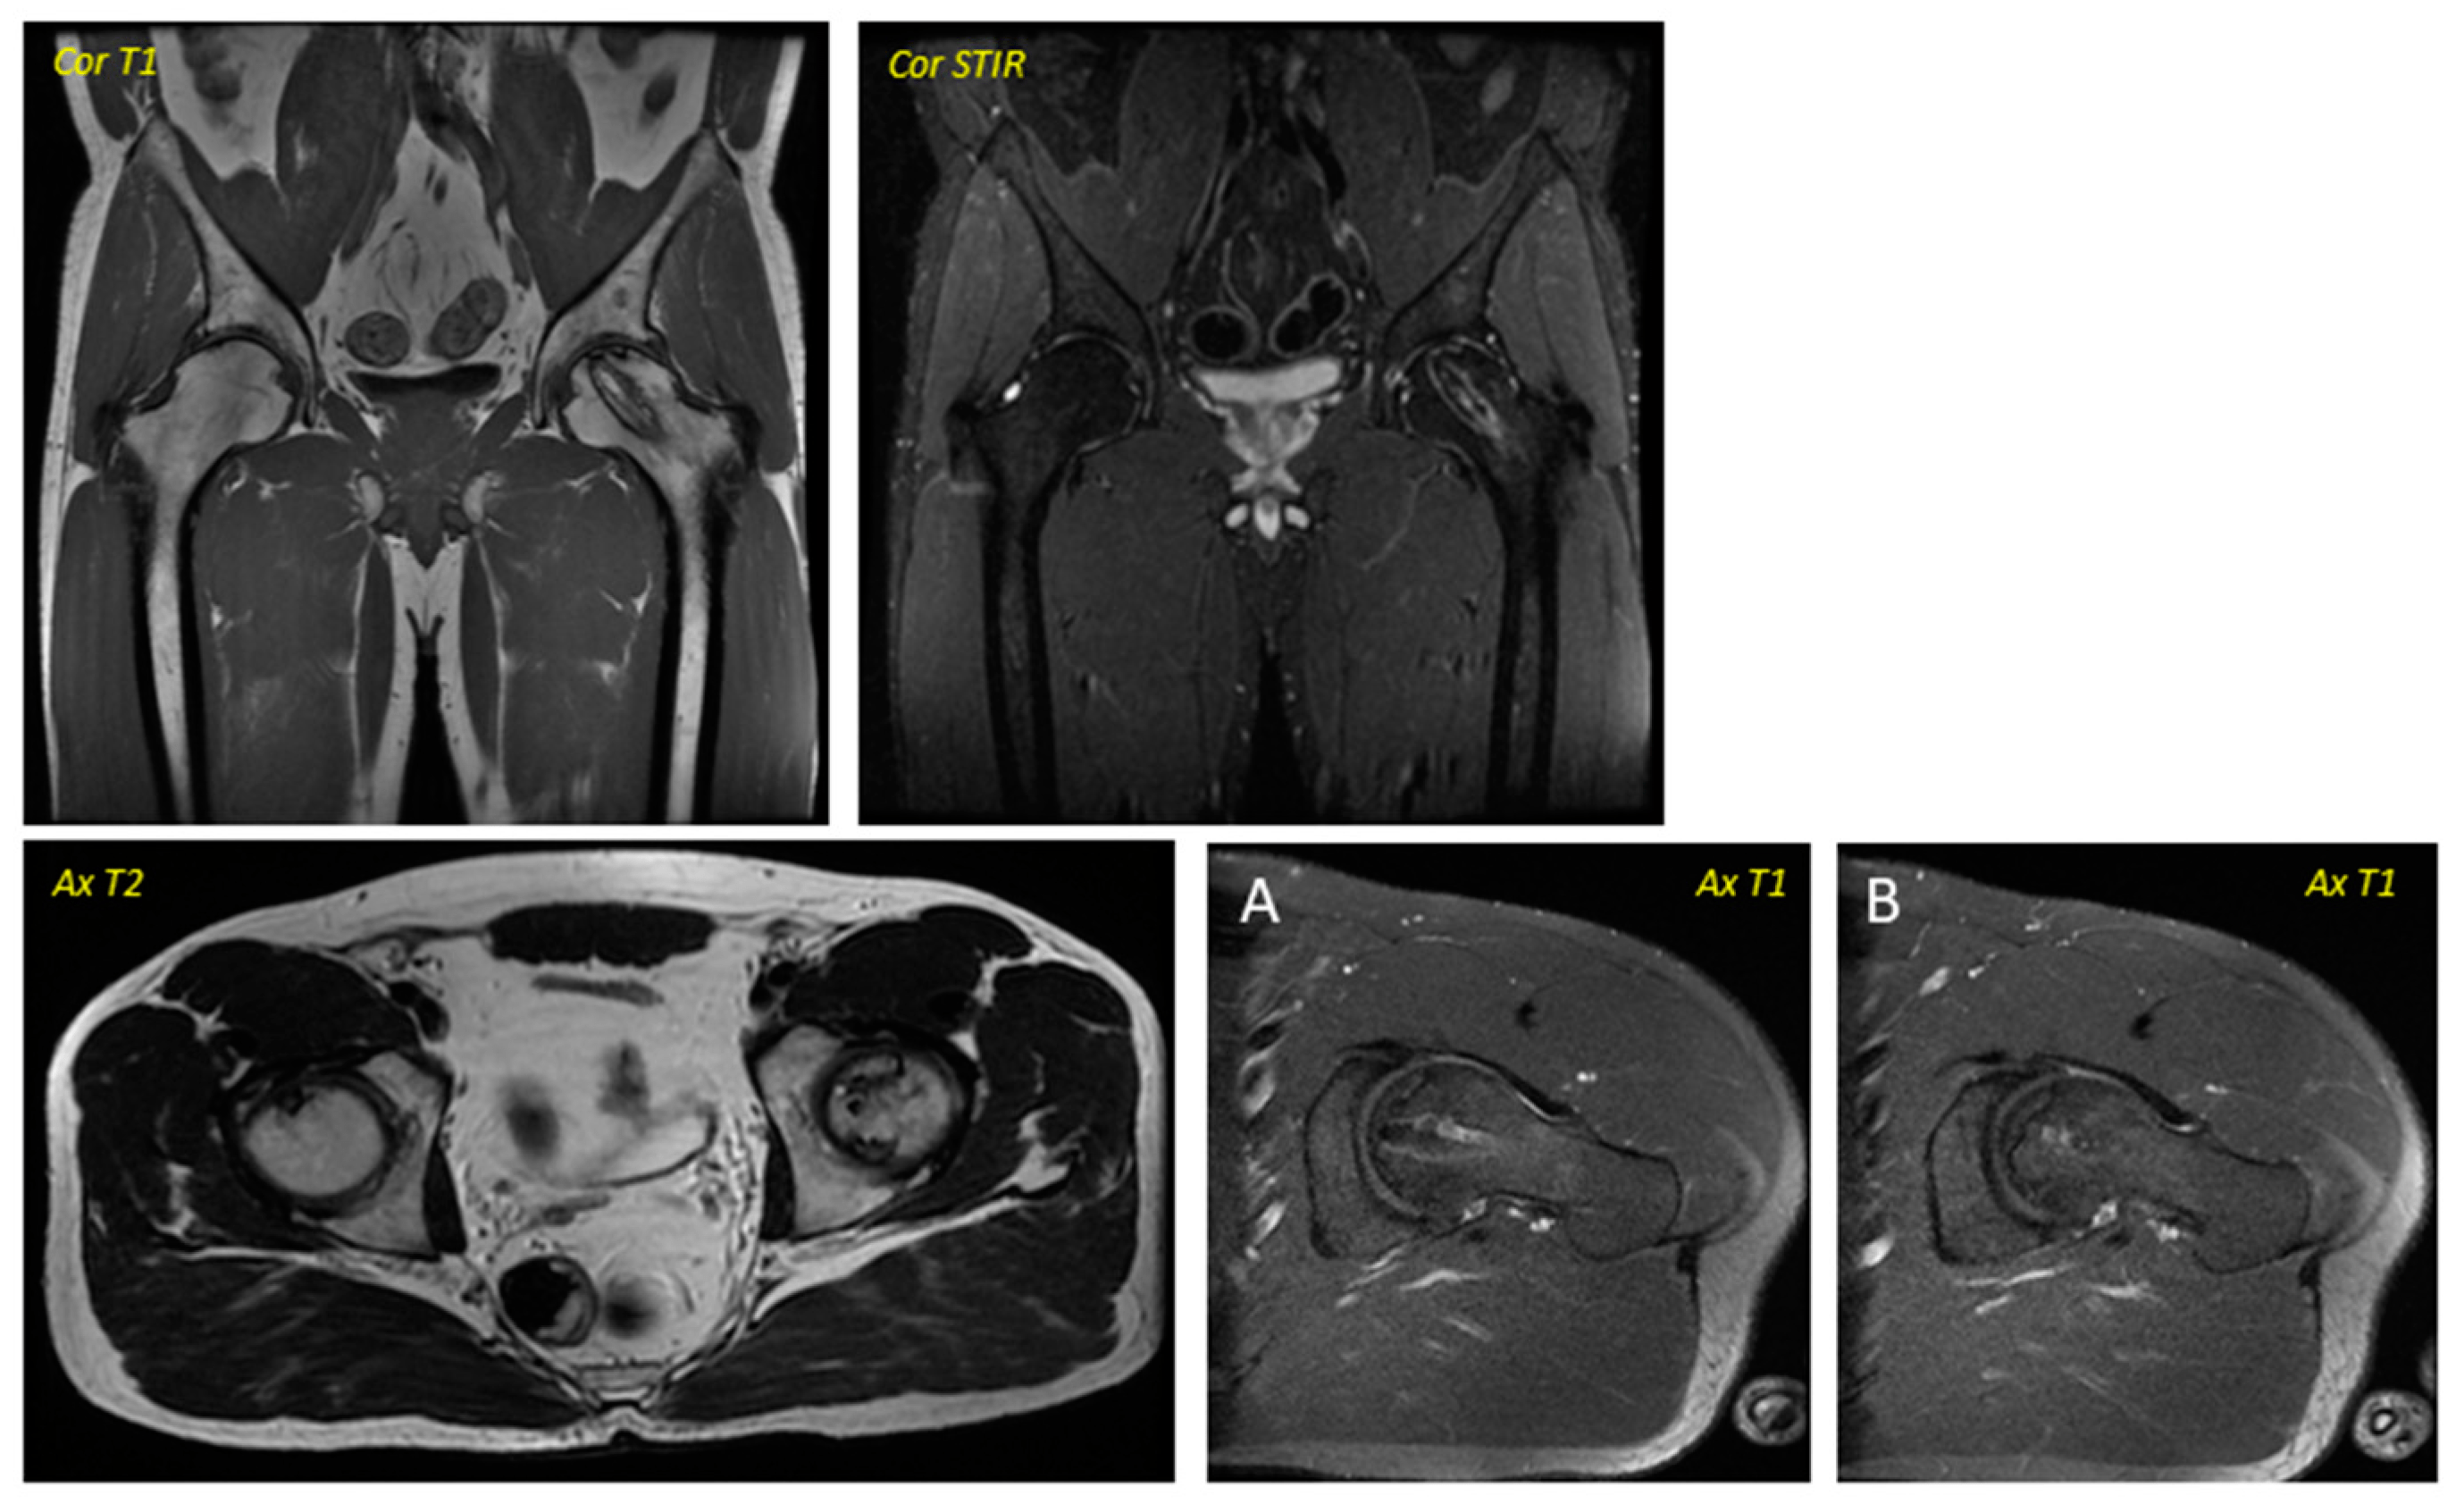

關(guān)于影像學(xué)研究,在12個(gè)月的隨訪(fǎng)期間,在影像學(xué)演變中觀(guān)察到了一些發(fā)現(xiàn)(圖1和圖2)。

首先,方向的變化從第六個(gè)月開(kāi)始出現(xiàn)在所有病例中,而在早期階段并不明顯。其次,62.5%的患者 ( n=5) 在手術(shù)后的第一年內(nèi)實(shí)現(xiàn)了影像穩(wěn)定。第三,兩名患者 (25%) 出現(xiàn)壞死區(qū)進(jìn)展,而一名 (12.5%) 患者出現(xiàn)明顯的再骨化跡象。盡管觀(guān)察到描述性差異,但后一個(gè)參數(shù)的p值在統(tǒng)計(jì)學(xué)上并不顯著。